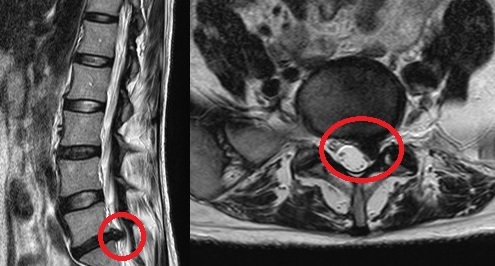

PELD (percutaneous endoscopic lumba discectomy) 내시경 레이저 디스크 수술은 허리 디스크로 인한 허리통증 및 하지 방사통을 완화하는 것을 목적으로 합니다. 허리 중앙에서 옆구리 10cm 정도 떨어진 위치에서 미세관을 디스크 속에 삽입하여 내시경을 이용해 모니터로 확인하면서 디스크에 병적인 수핵만을 제거하고 정상적인 수핵을 보존하는 수술입니다. 보존 요법과 수술 요법 사이에 있는 미세 또는 최소 침습 치료법으로 레이저를 사용하여 신경 압박으로 통증을 유발하는 수핵만을 제거하는 비관혈적 시술로 절개수술이 아니므로 신경, 근육에 손상을 주지 않습니다.

환자는 엎드린 상태에서 의사와 대화를 나누면서 국소마취를 합니다 국소 마취된 피부를 통해서 1mm 크기의 바늘을 영상증폭장치를 보면서 치료할 부위에 위치시킵니다 1mm 바늘을 통해서 가는 가이드를 넣고 점차 큰 가이드로 교체하여 넓혀서 7mm 크기의 내시경을 치료 부위에 위치 시킵니다 내시경을 통해서 탈출된 디스크 조각과 신경을 구별해서 보면서 신경을 구별해서 보면서 영상증폭장치로 수술 부위를 계속 확인하면서 탈출된 디스크 조각을 제거합니다